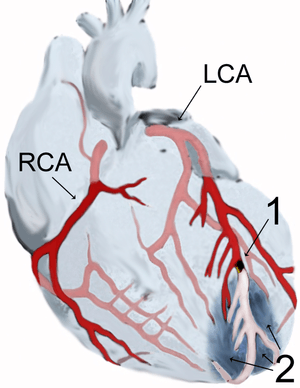

| Diagram of a myocardial infarction (2) of the anterior wall of the heart after blockage (1) of a branch of the left coronary artery (LCA). In the diagram, RCA is the right coronary artery. | |